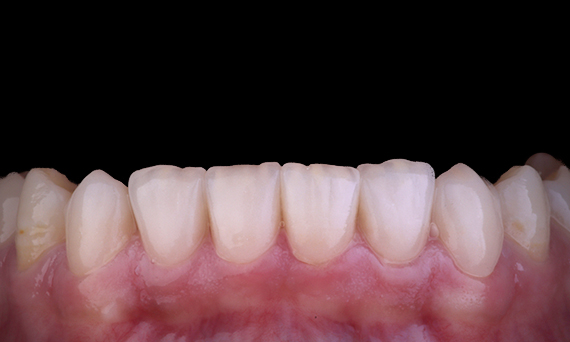

Minimal Preparation Veneers after Trauma of Upper Central Incisors

Restoration with a highly esthetic material in one day after trauma to the maxillary central incisors.

Before: Clinical Situation pre-op. Trauma of upper central incisors

After: Adhesively bonded restorations.

Dr. Mohamed Hassanien

Cairo, Egypt